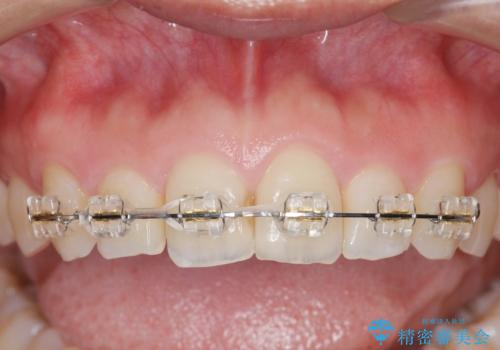

前歯のガタつきをきれいに マウスピース矯正治療

- 「前歯のガタつきをきれいにしたい。」と矯正治療を希望され来院されました。

前歯のガタつきをワイヤー部分矯正、上顎前突の咬合関係を後方移動することで理想的な咬合関係を確立します。

上顎の全体的な後方移動を実現するためにマイクロインプラントを併用したゴムかけを行ったことで理想的な咬合関係を確立することができました。